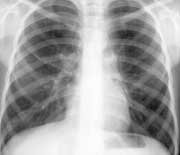

До 1995 года ребенок чувствовал себя удовлетворительно. Ухудшение состояния с 1996 года (Рис. 1): повышение температуры до 39 гр., ознобы, гнойная мокрота, в мокроте высевается золотистый стафилококк в сочетании с синегнойной палочкой.

Рис. 1. Изменения в легких при муковисцидозе на рентгенограмме.

Ребенок консультируется в институте туберкулеза проф.М.Н.Ломако, диагноз — "Двусторонняя бронхопневмония на фоне муковисцидоза", проф.И.И.Лозюк, диагноз — "Хроническая "ползучая" пневмония с локализацией в обеих верхних долях, продуктивно-деструктивная форма с объемным уменьшением долей и частичной обструкцией нижнедолевых бронхов".

Состояние ребенка остается достаточно тяжелым, учащаются обострения бронхолегочного процесса, ухудшается рентгенологическая картина, лабораторные показатели. На рентгенограммах имеют место деформация и обогащение легочного рисунка по сетчато-ячеистому типу за счет перибронхиальной реакции межуточной ткани, выраженная эмфизема, неоднородные с участками просветления затемнения в верхних долях обоих легких.